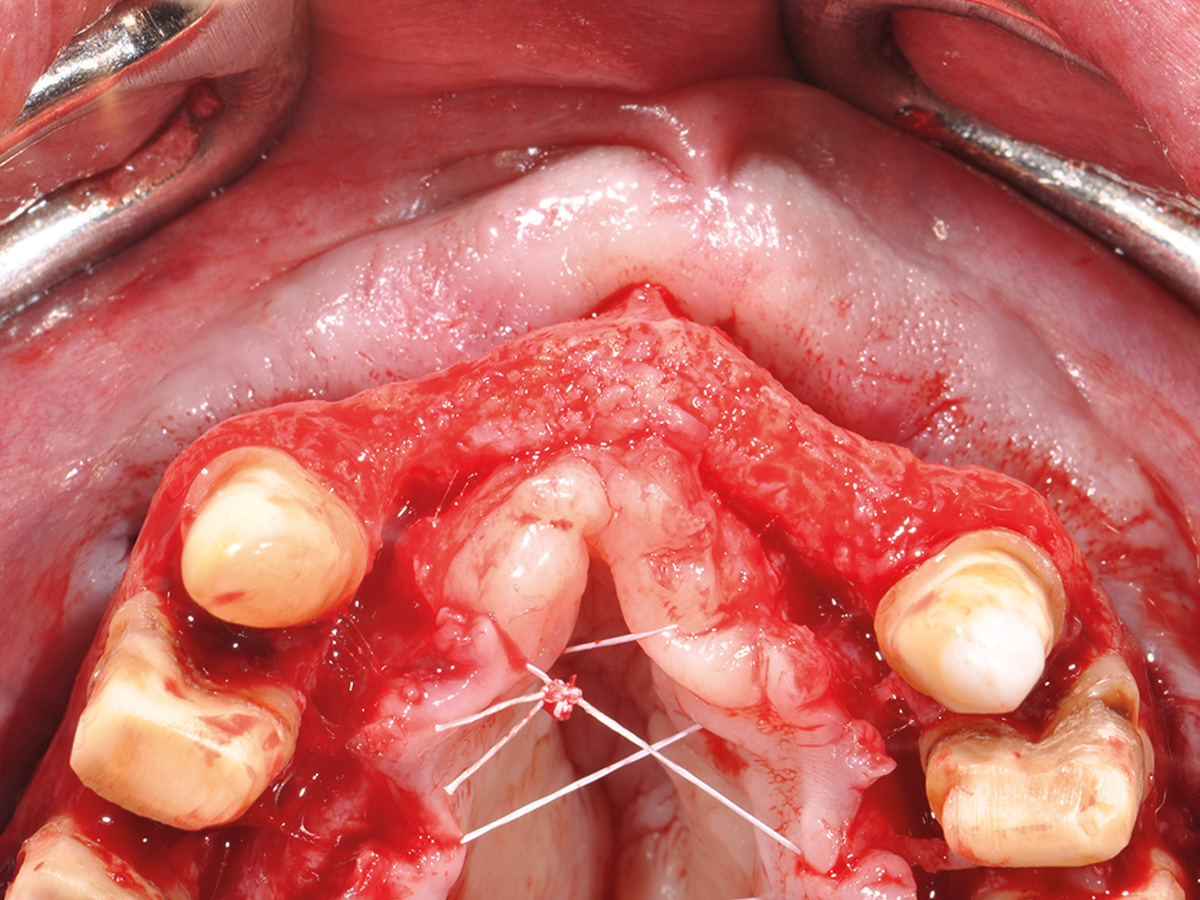

Im Anschluss werden am Tiermodell alle für eine vorhersehbare Augmentation notwendigen Techniken im Sinne des „Simplify your Augmentation“ eingeübt. Der Weg führt von der einfachen Membrananwendung über die Bone-Lamina- und Double-Layer-Technik bis zur Bone-Shield-Technik. Das Bone Shield ist eine Evolution der klassischen Schalentechnik und erlaubt es, auch komplexe vertikale und kombinierte Augmentationsfälle

im Rahmen der im Kurs vorgestellten Konzeption sicher zu lösen.